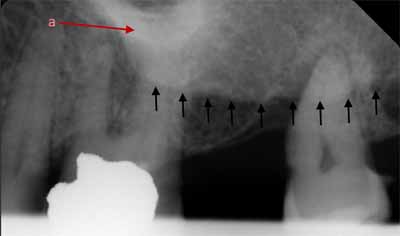

歯槽骨に、薄くわずかに湾曲したエックス線透過性の線が見えることがあります。これらは栄養管であり、神経と血管のための骨内の小さな空洞です (画像5を参照)。多くの場合、上顎洞の壁でもこれらの栄養経路を識別できます。